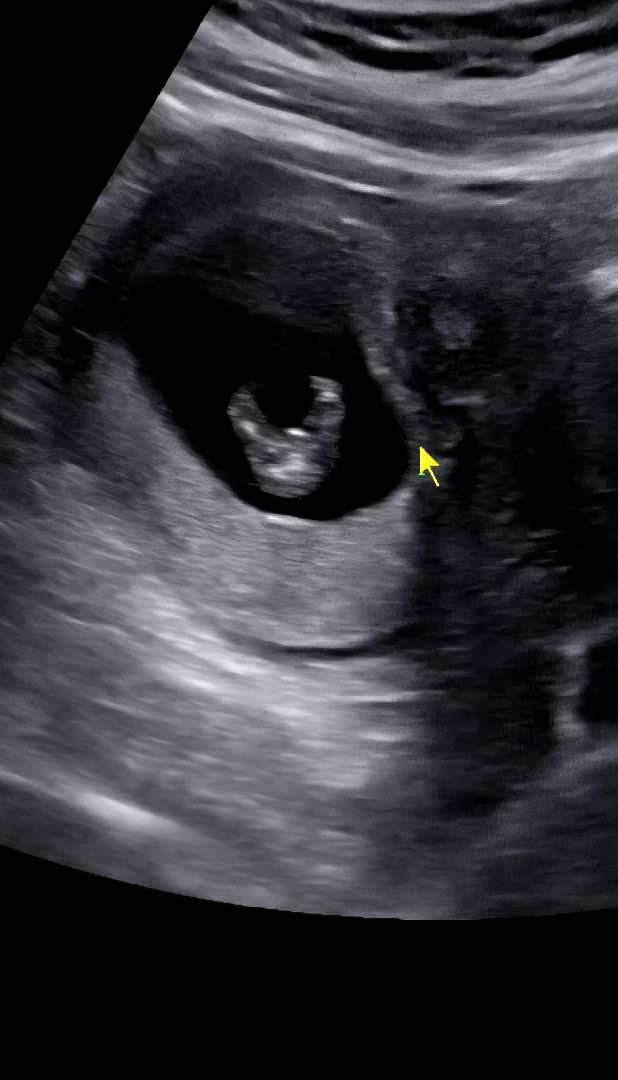

안녕하세요! 11주 2일은 성별 알아보기 아직일까요? ㅎㅎㅎ

오늘 초음파에 두다리 번쩍 장면이 우연히 찍혔는데 혹싀.. 아직 뭐 알순 없는 단계일까요 아니면 조금이라도 유추할 수 있을까요? 한 번 봐 주시면 감사하겠습니다!!!!

이 시기에는 생식기가 다 튀어나와 있어서 다리 사이로 성별 구분 불가해요! 생식기 함께 나온 옆에서 찍은 게 필요해용!

이런 사진 괜찮을까요? ㅎ

생식기인지 확실하진 않지만 맞다면 딸 같아요ㅎㅎ